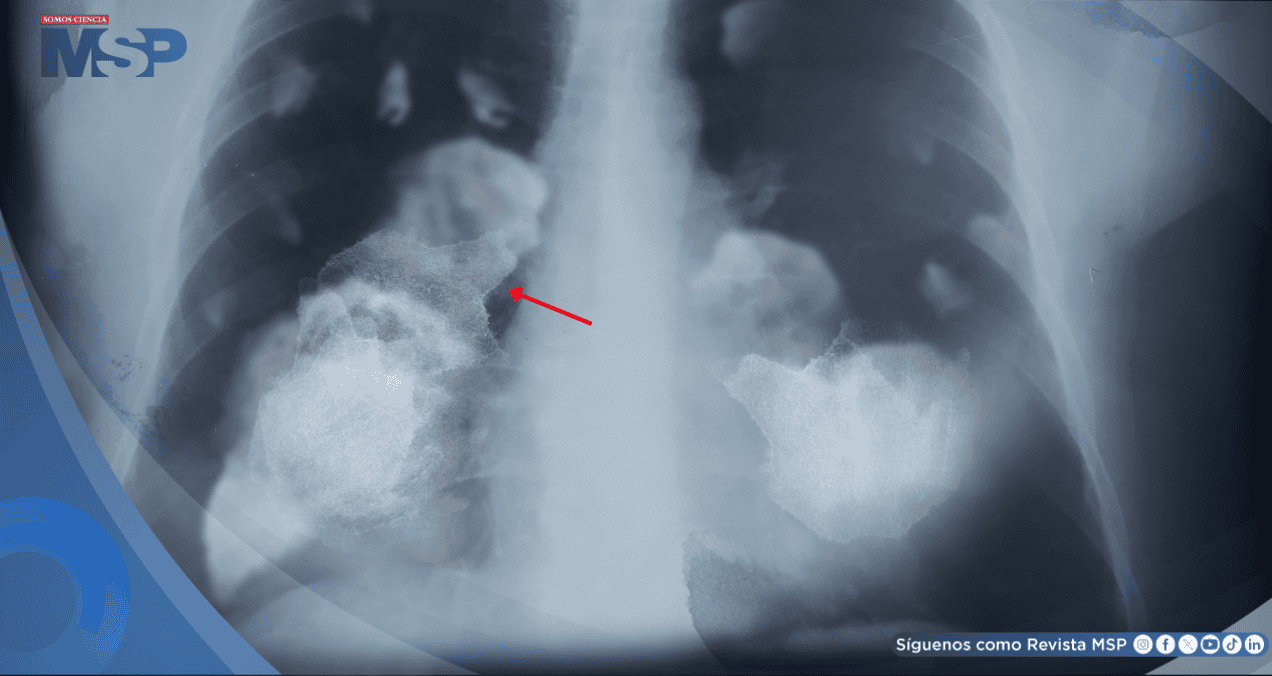

El análisis de 871 tumores pulmonares en no fumadores reveló que vivir en zonas contaminadas se asocia a mutaciones relacionadas con el envejecimiento y el tabaquismo, así como a telómeros más cortos, un signo de envejecimiento celular acelerado.

La investigación reveló que la polución no solo incrementa el número total de mutaciones en el ADN, sino que también acelera el envejecimiento celular. Los pacientes expuestos a altos niveles de contaminación mostraron telómeros significativamente más cortos -los extremos protectores de los cromosomas-, un marcador clave de estrés celular.